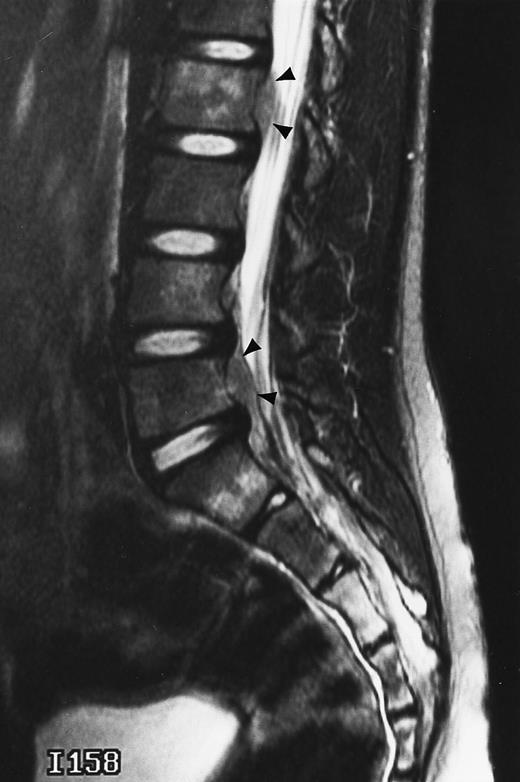

T1-weighted (500/11, TR/TE) sagittal MR images of the lumbosacral spine in a 45-year-old woman before (A) and 40 days after (B) bone marrow transplantation for multiple myeloma. There is a diffuse MR pattern of marrow involvement in (A) (bone marrow plasma cells, 50%; monoclonal protein, 6.0 g/dL). On the posttreatment image, there is definite reinstitution of fatty marrow in the spine and, in particular, around the basivertebral veins, in keeping with partial response to treatment (bone marrow plasma cells, 0.5%; monoclonal protein, 1.6 g/dL).